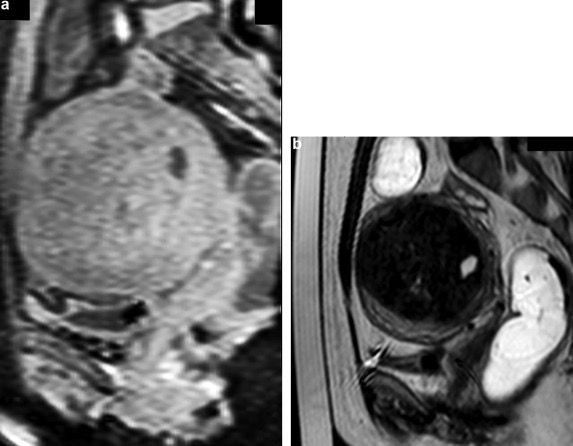

Le système d’imagerie embarquée associé à l’HIFU repose soit sur une échographie en temps réel (via une sonde d’USD intégrée), soit sur une IRM, dans laquelle l’appareil est placé dans le tunnel afin d’assurer un guidage par cartographie thermique (figure 3). Ce système d’imagerie permet de localiser précisément la cible (prostate, fibrome, tumeur hépatique), d’assurer le suivi thermique en temps réel et de contrôler le déplacement du foyer acoustique.

Figure 3 : Exemple de configuration HIFU pour le traitement de fibromes utérins [17]

Parfois, la procédure se déroule directement sous IRM. Cela permet d’utiliser des séquences sensibles à la température pour suivre en temps réel l’échauffement des tissus, tout en contrôlant précisément la position du patient. Ce guidage continu aide à maintenir le ciblage optimal du volume à traiter et à sécuriser l’ensemble du geste (figure 6).

Figure 8 : IRM de fibrome utérin avant (gauche) et après (droite) traitement par HIFU. On observe un centre nécrotique à droite, symbole d’une thermodestruction par les ultrasons [27]